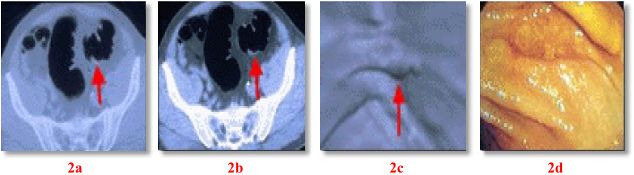

Research has shown that Virtual Colonoscopy is better able to see polyps than Barium Enema and is nearly as accurate as Conventional Colonoscopy. Fig. 1 shows a polyp and Fig. 2 a flat cancer seen on 3 techniques: 2D axial CT (Fig. 1a, 2a-b), 4D VC (Fig. 1b, 2c), and conventional colonoscopy (Fig. 1c, 2d). Most patients report that the Virtual Colonoscopy technique is more comfortable than either Barium Enema or Conventional Colonoscopy. Studies suggest a very high sensitivity and specificity (96%) for the detection of polyps 1 cm or greater. Such polyps have significant malignant potential. Sensitivity for polyps less than 1 cm is significantly less. Although controversy exists as to the definition of a "significant" polyp with regard to size, polyps < 1 cm in size have a low probability of malignancy and the likelihood of any single lesion progressing to cancer is also small.